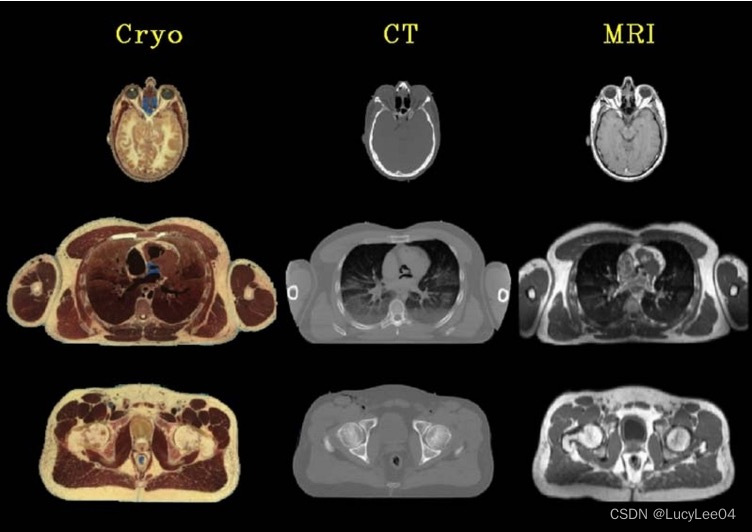

图像的正确重建与可视化

多模态扫描图像的配准